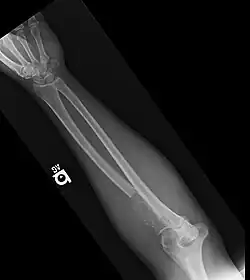

• Bone lesions: one or more osteolytic lesions on skeletal radiography, CT, or PET/CT. * (If bone marrow has less than 10% clonal cells, more than one bone lesion is required to distinguish from solitary plasmacytoma with minimal marrow involvement.)

Radiology Normal bone X-rays or solitary bone lesion advanced lytic bone lesions

("extensive skeletal destruction and major fractures")